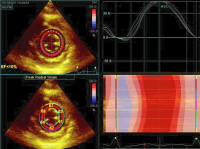

Strainanalyse

Abbildung 8: Strainanalyse (offline) der Raumforderung. Keine intrinsische Kontraktilität (rote Linie) im Vergleich zum linken und rechten Ventrikel.